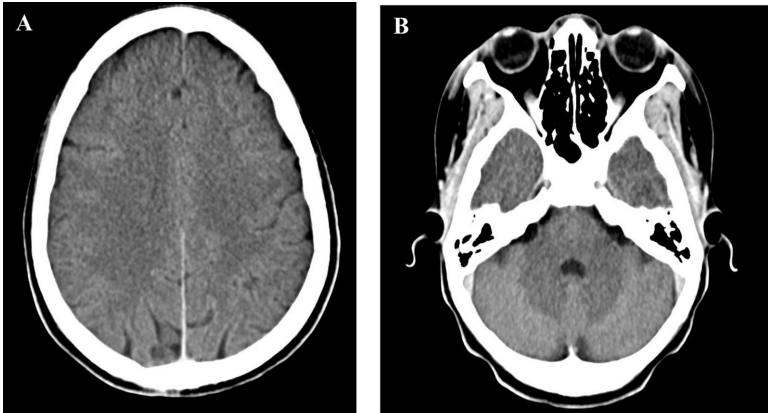

本刊推荐:研究人员针对撒哈拉以南非洲地区罕见病诊断困境,开展难治性成人斯蒂尔病(AOSD)的临床诊疗研究。通过详细报道一例28岁女性患者的诊疗历程,证实结合Fautrel和Yamaguchi诊断标准、血清铁蛋白糖基化比例(<20%)与影像学检查可实现AOSD的准确诊断。该研究为资源有限地区AOSD的鉴别诊断提供了重要参考,强调需警惕非典型临床表现及并发症。